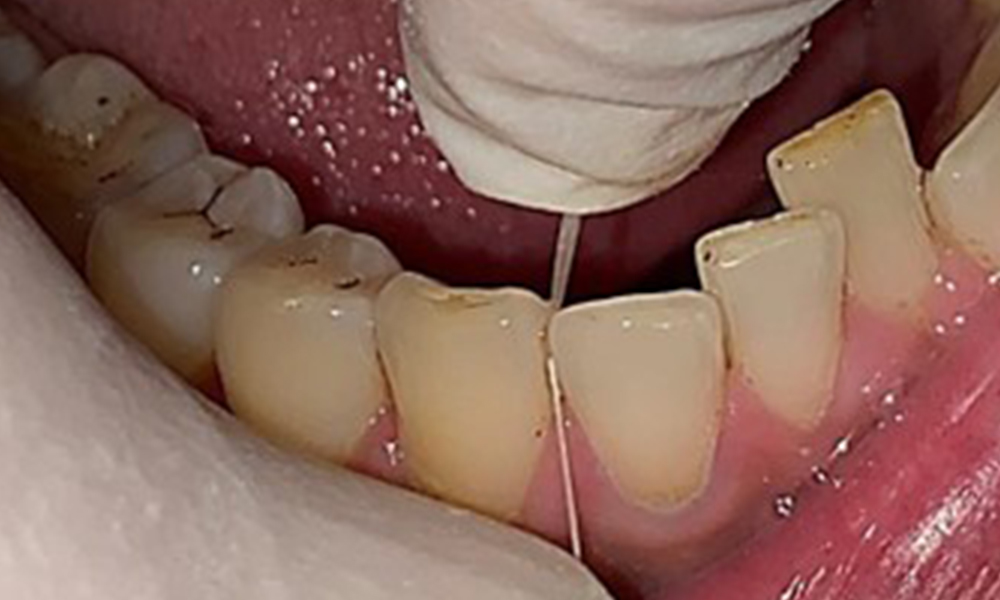

Extraoral sind keine pathologischen Befunde festzustellen, intraoral zeigen sich bei der Frontalansicht im Bereich der keratinisierten Gingiva und am Übergang zur beweglichen Schleimhaut bräunlicheVerfärbungen (Abb. 2), welche auf den Nikotingenuss zurückzuführen sind. Am Gaumenbereich zeigen sich insbesondere im Bereich Oberkiefermolaren palatinal weißliche Schleimhautveränderungen, die ein Hinweis auf einen erhöhten Verhornungsgrad sind und ebenso auf den Nikotingenuss zurückzuführen sind. Die Zunge ist mit einem weiß-bräunlichen abwischbaren Belag versehen.

Dental zeigt sich ein vollbezahntes Gebiss mit 28 Zähnen. Auffällig sind Erosionen und Attritionen

(Abb. 4, Abb. 5). Der Patient trägt seit vielen Jahren nachts eine Schiene mit adjustiertem Aufbiss aufgrund Bruxismus. Die Erosionen sind auf den langjährigen Konsum isotonischer Getränke zurückzuführen. Parodontaler Knochenverlust und aktive kariöse Läsionen sind nicht vorhanden.